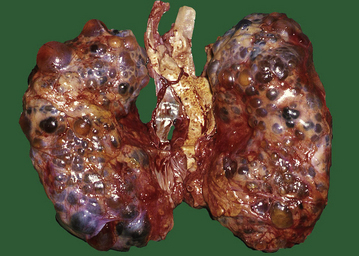

Autosomal dominant polycystic kidney disease (ADPKD)

ADPKD is the primary renal disease in 8% of adult patients in the European Dialysis and Transplantation Registry. The condition is always bilateral; the kidneys are grossly enlarged, each commonly weighing 1000g or more (Fig. 21.4). The kidneys are distorted by numerous cysts, from a few millimetres up to c. 100 mm in diameter, with thin bands of renal parenchyma compressed between them. Most cysts contain clear fluid, but previous haemorrhage can result in the contents being brown due to haemosiderin. The cysts are formed at all levels of the nephron.

image

Fig. 21.4 Autosomal dominant polycystic disease (ADPKD). Both kidneys are greatly enlarged by numerous cysts of varying sizes.

ADPKD is inherited as an autosomal dominant trait with a high degree of penetrance; this is relevant to genetic counselling and screening. Most cases are linked to the alpha-globin cluster on the short arm of chromosome 16 (PKD 1) which encodes polycystin-1; the remainder are due to mutations on chromosome 4 (PKD 2) which encodes polycystin-2. This condition presents at any age from childhood to late adult life. Renal function is maintained until the enlarging cysts press on the adjacent parenchyma, causing ischaemic changes leading to hypertension or renal failure. There is an association with berry aneurysms of the circle of Willis, a frequent source of often fatal subarachnoid haemorrhage (Ch. 26). Cysts also occur within the liver, pancreas and lungs, but have no functional significance in these organs.